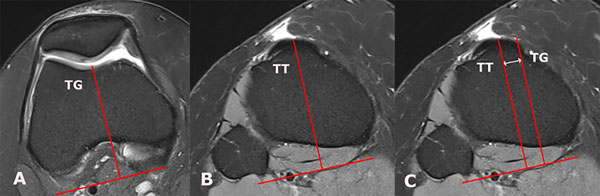

El aumento en la distancia TT-TG es el tercer factor de riesgo mayor.4 A diferencia de la displasia troclear y la rótula alta, este no es capaz de provocar por sí solo una luxación patelar. Esta medición es una representación en el plano axial del ángulo Q, por lo que su medición se ve afectada tanto por la rotación femoral/tibial como por la alineación coronal de la extremidad17 (fig. 3). Ha demostrado alterar el tracking patelar aumentando las fuerzas entre la rótula y la faceta lateral de la tróclea. Su medición ha sido propuesta tanto en TC como en RM con valores de corte diferentes.18

Figura 3: Medición en cortes axiales de RM de la distancia entre la tuberosidad anterior de la tibia y el surco troclear (TT-TG) utilizando como referencia los cóndilos posteriores. A) Punto más posterior del surco troclear (TG). B) Punto central del tendón patelar en la tuberosidad anterior de la tibia (TT). C) Medición de la distancia TT-TG en un mismo corte axial.